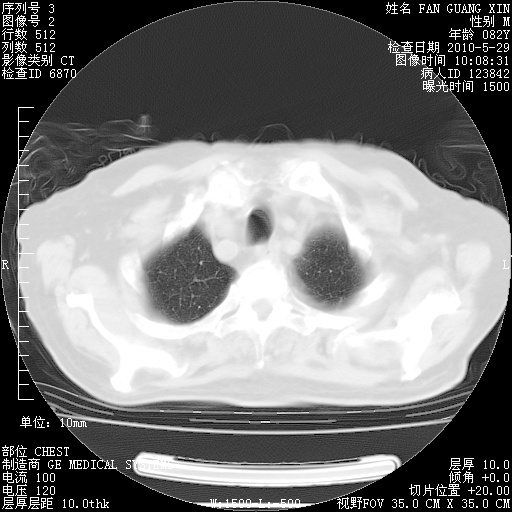

再治疗10天后的肺部CT